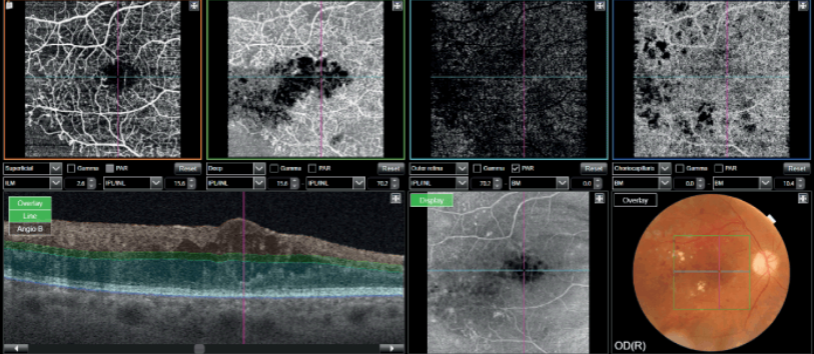

From macular degeneration to diabetic retinopathy, we employ the latest techniques and treatments. Using state-of-the-art imaging, we monitor and manage retinal conditions ensuring the best outcomes possible.

Ophthalmology requires a lot of technology because the eye is both small yet incredibly complex, with 80% of external input to the brain processed by the visual system. For example, some eye diseases like diabetic eye disease can cause thickening in the nerve layer measured in micrometers.

Technology aids clinical eye examination in diagnosis and monitoring of your eye condition by taking away the subjectivity through precise measurements and grading. The powerful imaging technology we have also allows our patients to better visualise and understand their condition. We also employ technology for treatment and surgery to bring about our aim of good outcomes and quicker recovery.

Diagnostic capability Seeing deeper makes it possible to have a better understanding of many ocular pathologies2. With features such as OCT Angiography1, Fundus Autofluorescence* and En Face OCT, Triton empowers clinicians with multimodal imaging capability to help assess and preserve patient’s eye health.